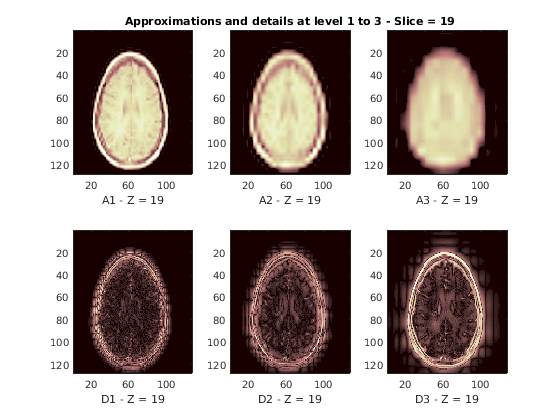

Восстановленные приближения и детали вдоль Z-ориентации отображены ниже.

nbIMG = 6; idxImages_New = [1 7 10 16 19 25]; for ik = 1:nbIMG j = idxImages_New(ik); figure('DefaultAxesXTick',[],'DefaultAxesYTick',[],... 'DefaultAxesFontSize',8,'Color','w') colormap(map) for k = 1:n labstr = [int2str(k) ' - Z = ' int2str(j)]; subplot(2,n,k) image(A{k}(:,:,j)) xlabel(['A' labstr]) if k==2 title(['Approximations and details at level 1 to 3 - Slice = ' num2str(j)]) end subplot(2,n,k+n) imagesc(abs(D{k}(:,:,j))) xlabel(['D' labstr]) end end